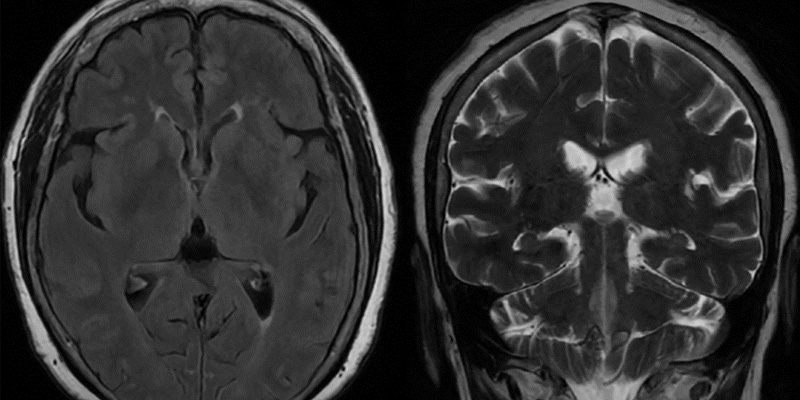

Chẩn đoán hình ảnh (MRI, CT, PET-CT)

MRI não

Đây là tiêu chuẩn vàng trong phát hiện ung thư não, cho thấy:

- Kích thước, vị trí và ranh giới khối u

- Mức độ xâm lấn

- Phù não xung quanh

MRI có phát hiện được ung thư não không?

Có. MRI là phương pháp chính xác nhất để phát hiện khối u trong não.